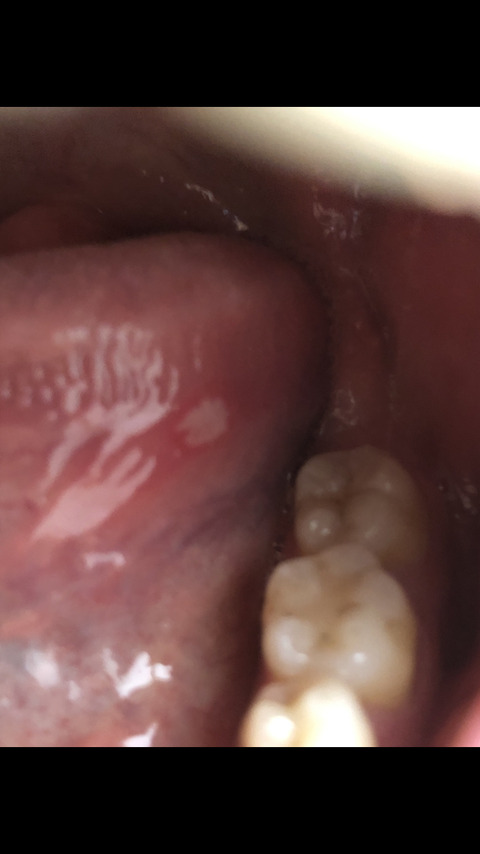

口内炎

普通に舌癌やろ

写真じゃ断定はできんけど多分口内炎やろ

研修医やが二週間とか三週間治らん口内炎を見たら舌癌を疑えってのを昔口腔外科で習った

ガチで口腔外科行け

ワイ歯医者、それアフタ性口内炎やぞ

典型的なアフタ

傷ついたとか明確な理由がないなら潰瘍より原因のほうを気にしたほうがええで